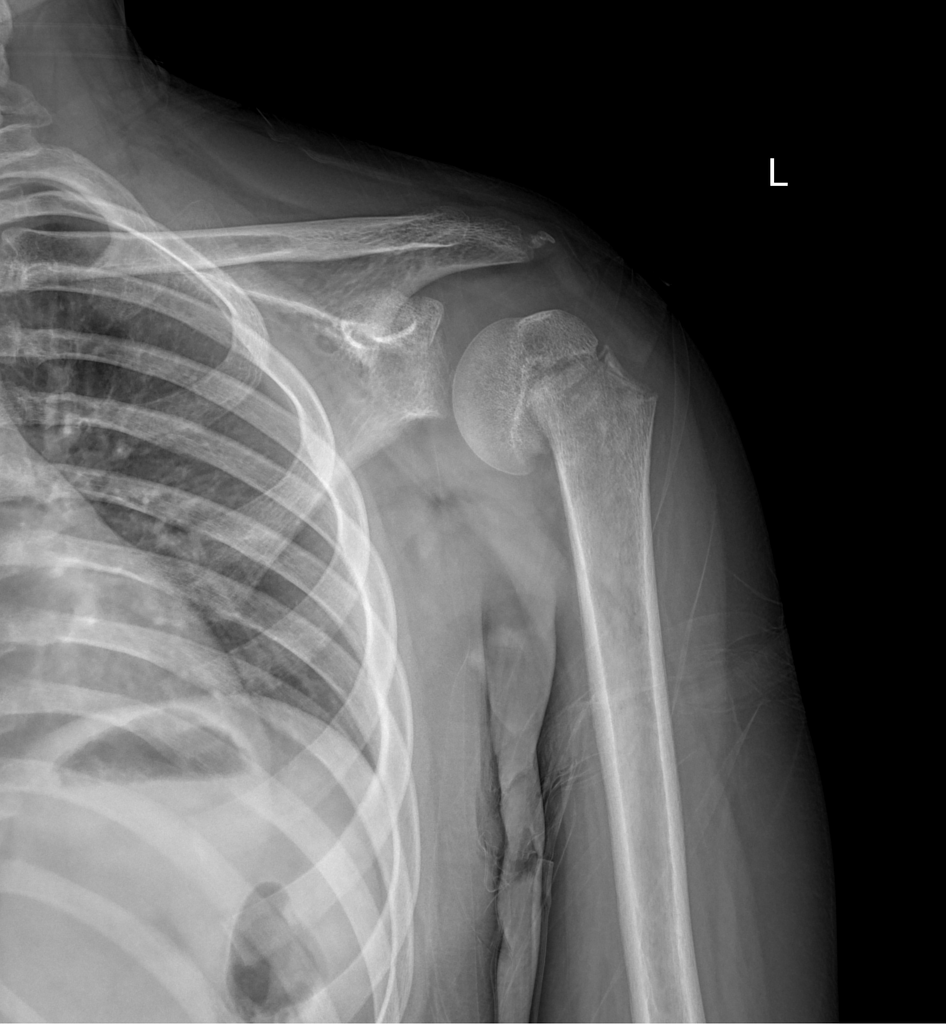

Salut les amis 🎉 Homme de 65 ans, chute au volley-ball. Votre diagnostic précis ? 🌐 Interprétation : https://t.co/cInj5CT7pZ #Radiologie #EDN